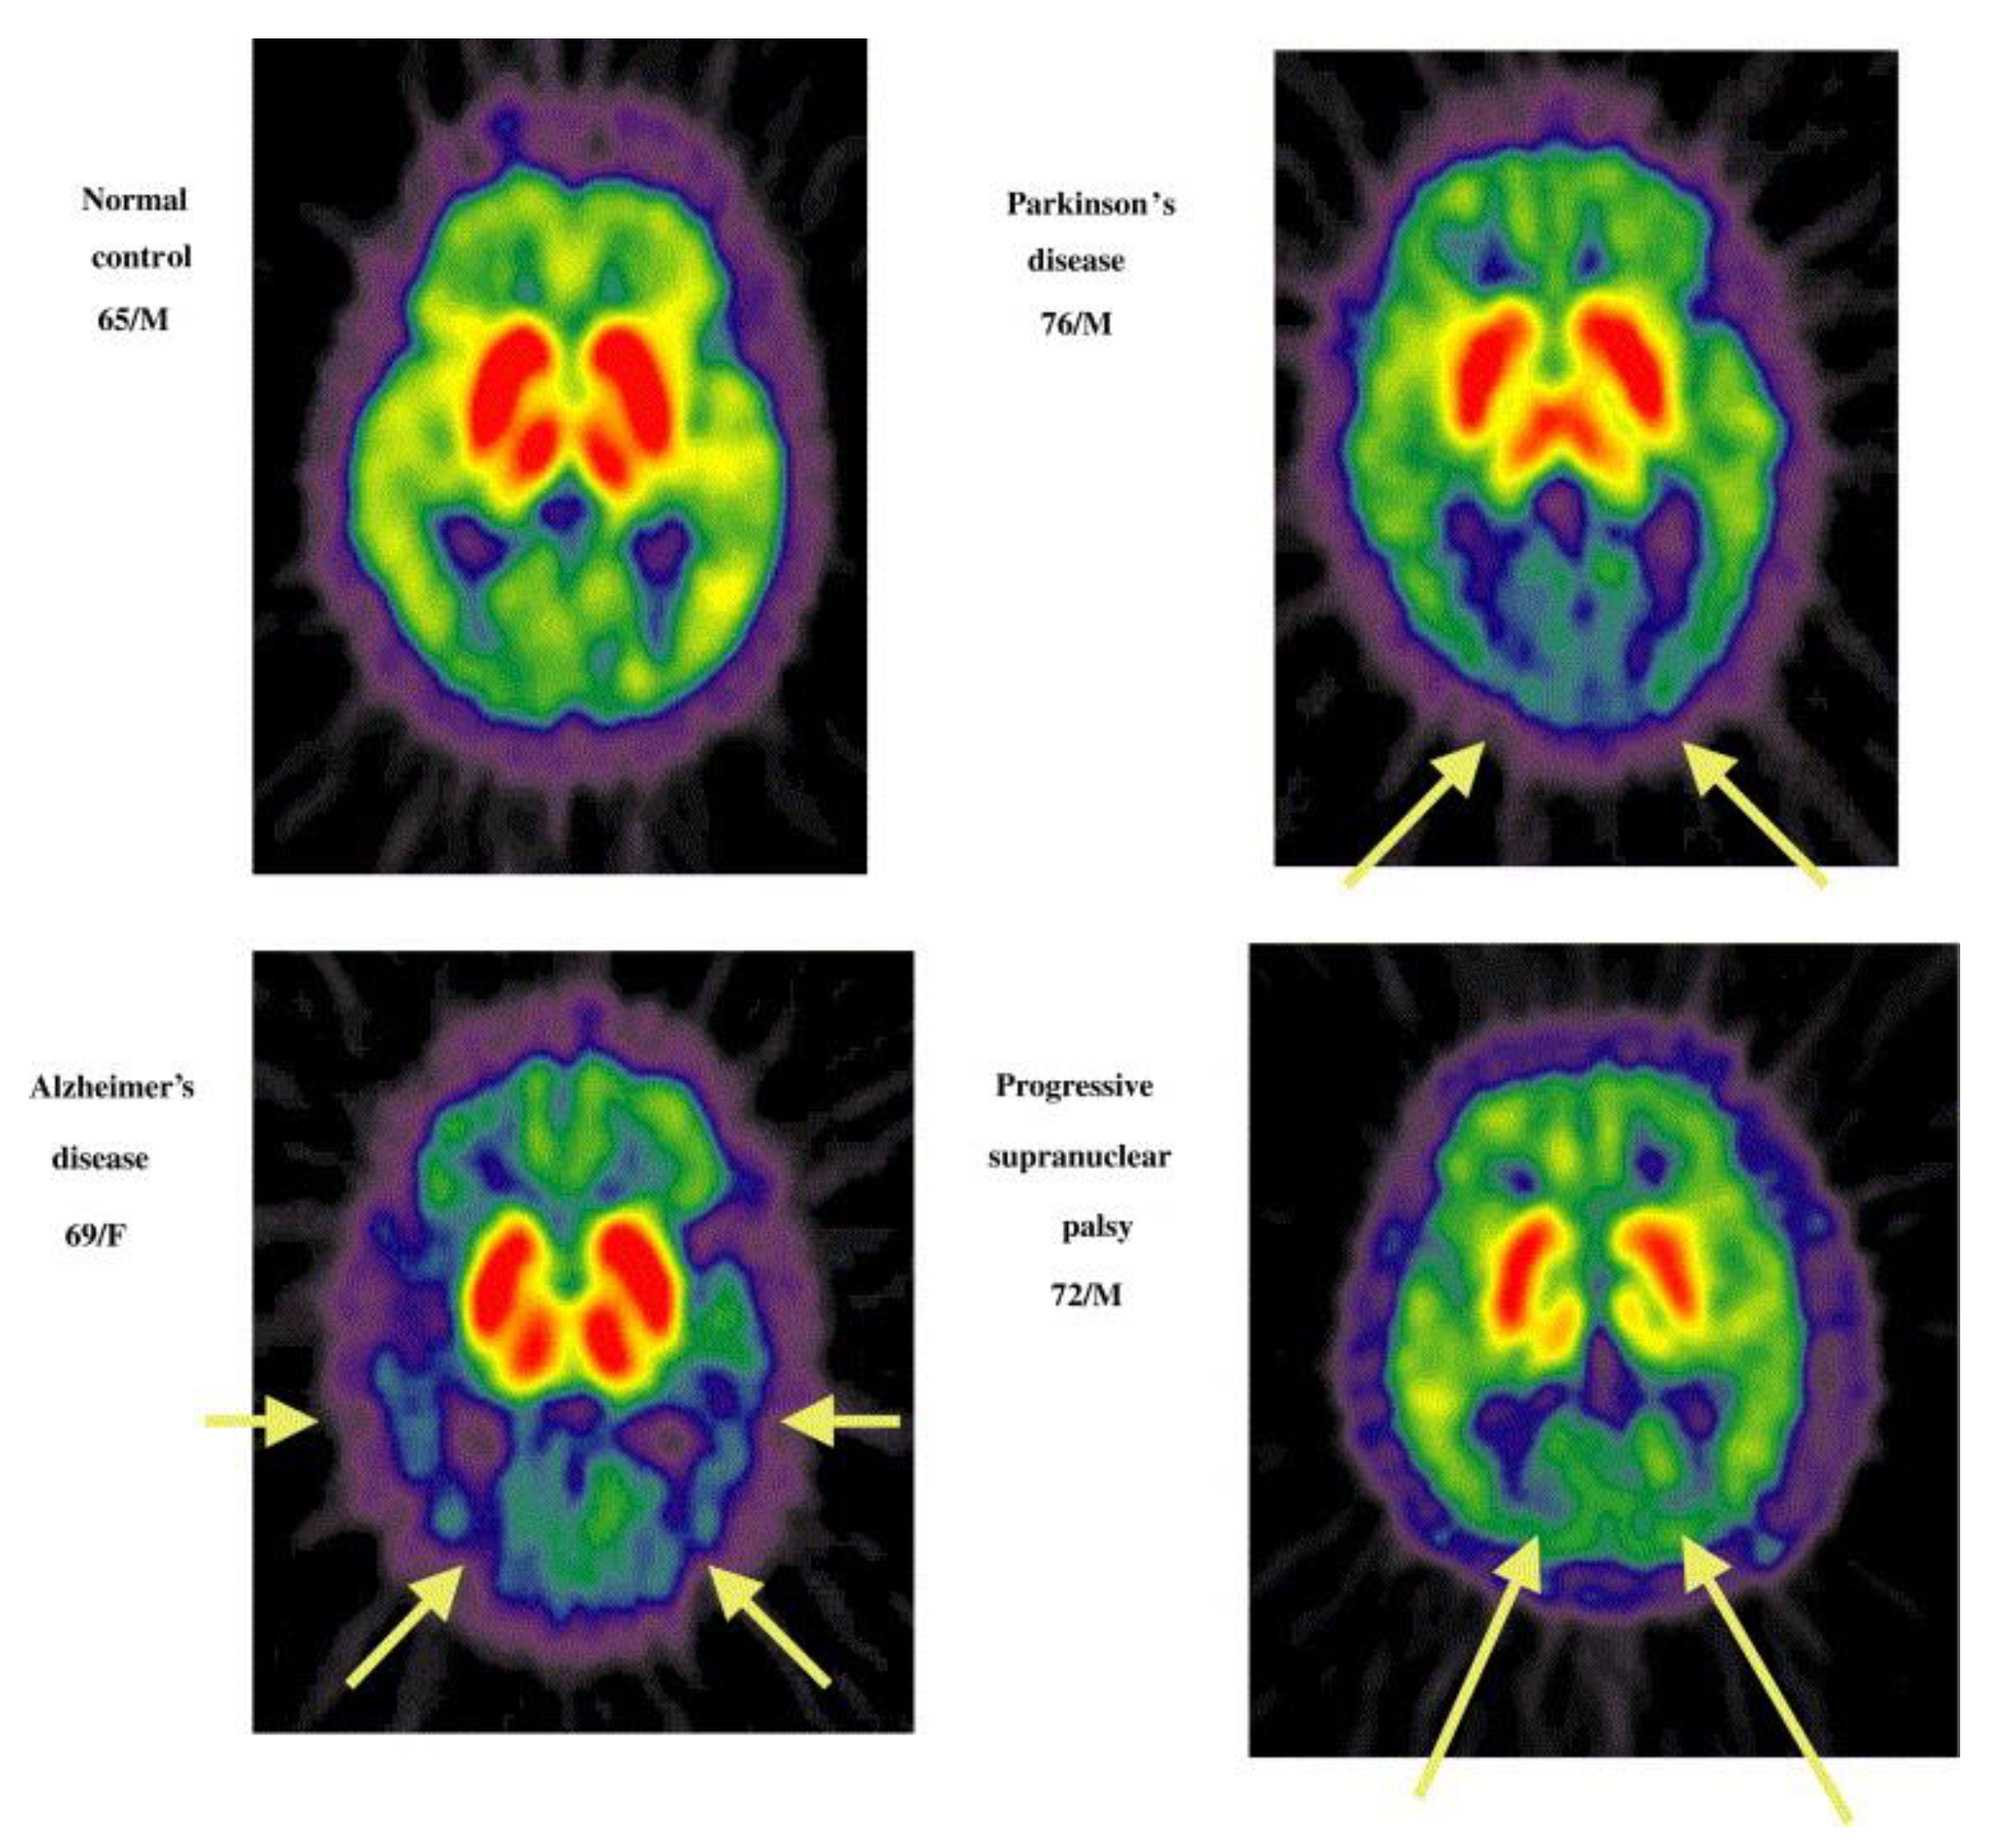

- Shinotoh, H.; Namba, H.; Yamaguchi, M.; Fukushi, K.; Nagatsuka, S.; Iyo, M.; Asahina, M.; Hattori, T.; Tanada, S.; Irie, T. Positron emission tomographic measurement of acetylcholinesterase activity reveals differential loss of ascending cholinergic systems in Parkinson’s disease and progressive supranuclear palsy. Ann. Neurol. 1999, 46, 62–69. [Google Scholar] [CrossRef] [PubMed]